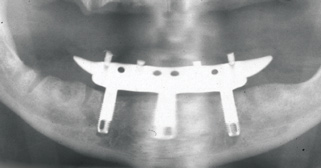

Fig 17. A three-implant fixed bridge may be an immediate-load alternative for a fixed restoration as opposed to a two-implant overdenture. In addition to significant cost reduction due to pre-manufactured components, the final long-term restoration is delivered on the day of surgery.

Figure 17

As an alternative to the relatively expensive traditional hybrid restoration that the senior population may perceive as unattainable at their age, an immediate-load all-resin provisional may often be a reasonable option as an entry-level prosthesis. This can serve for extended periods or indefinitely, and when made with a sufficient volume of resin and opposing a light occlusion such as a maxillary denture, it can offer the benefit of fixed retention at a significant reduction in expense (Figure 15 and Figure 16). Technology involving a guided approach for placing three implants universally in the same sites with pre-manufactured, one-size-fits-all bar components in the mandible can now allow placement of a final restoration in one day, again at a significantly reduced cost (Figure 17 and Figure 18).24-26 Both of these fixed options—the resin long-term provisional and the three-implant bridge—are economically comparable to the most commonly considered implant prosthesis for elderly patients, the two-implant overdenture. In contrast to the latter, however, both fixed restorations offer significant advantages in bite force, bone preservation, maintenance, and patient satisfaction that are simply unachievable with the removable implant overdenture prosthesis.27-31